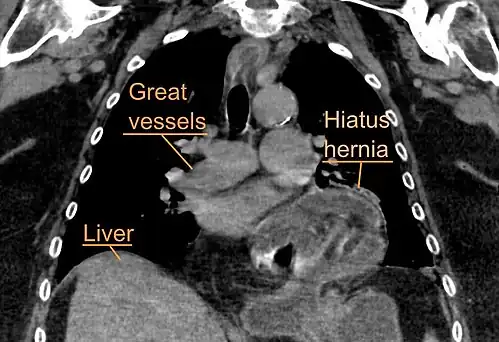

The diagnosis of a hiatal hernia is typically made through an upper GI series, endoscopy, high resolution manometry, esophageal pH monitoring, and computed tomography (CT). Barium swallow, as in the upper GI series, allows the size, location, stricture, and stenosis of oesophagus to be seen. It can also evaluate the oesophageal movements. Endoscopy can analyse the esophageal internal surface for erosions, ulcers, and tumours.

Meanwhile, manometry can determine the integrity of esophageal movements and the presence of esophageal achalasia. pH testing allows the quantitative analysis of acid reflux episodes. A CT scan is useful in diagnosing complications of hiatal hernia, such as gastric volvulus, perforation, pneumoperitoneum, and pneumomediastinum.[8]